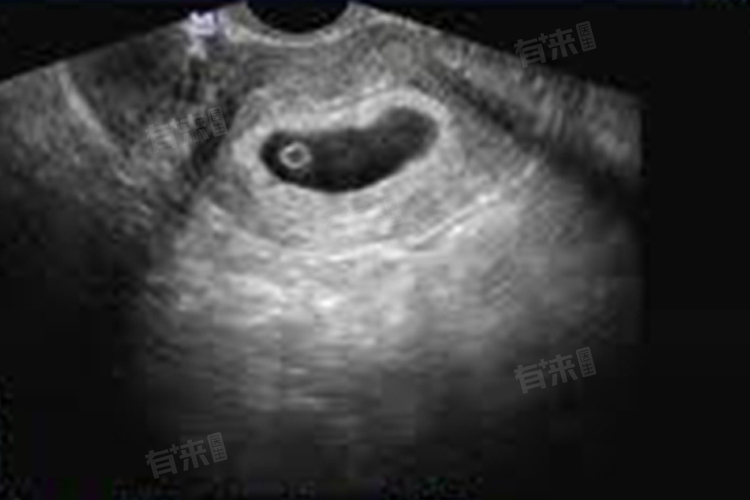

- 从受精卵形成到着床,需要6至7天。着床后,胚胎开始逐渐发育,孕囊也随之慢慢形成。在怀孕早期,孕囊的大小和形态都在不断变化。对于月经周期规律,周期为28至30天的女性来说,在怀孕35天左右,若通过阴道超声检查,有可能看到宫腔内的孕囊。这是因为阴道超声的探头更接近子宫,图像分辨率相对较高,能够更早发现较小的孕囊。

- 然而,若采用腹部超声检查,由于腹部脂肪、肠道气体等因素的干扰,可能需要怀孕40天左右才能较为清晰地看到孕囊。腹部超声检查时,需要充盈膀胱,将肠道推开,以获得更清晰的子宫及附件图像。在怀孕40天左右,孕囊已经发育到一定大小,在腹部超声下更易被识别。